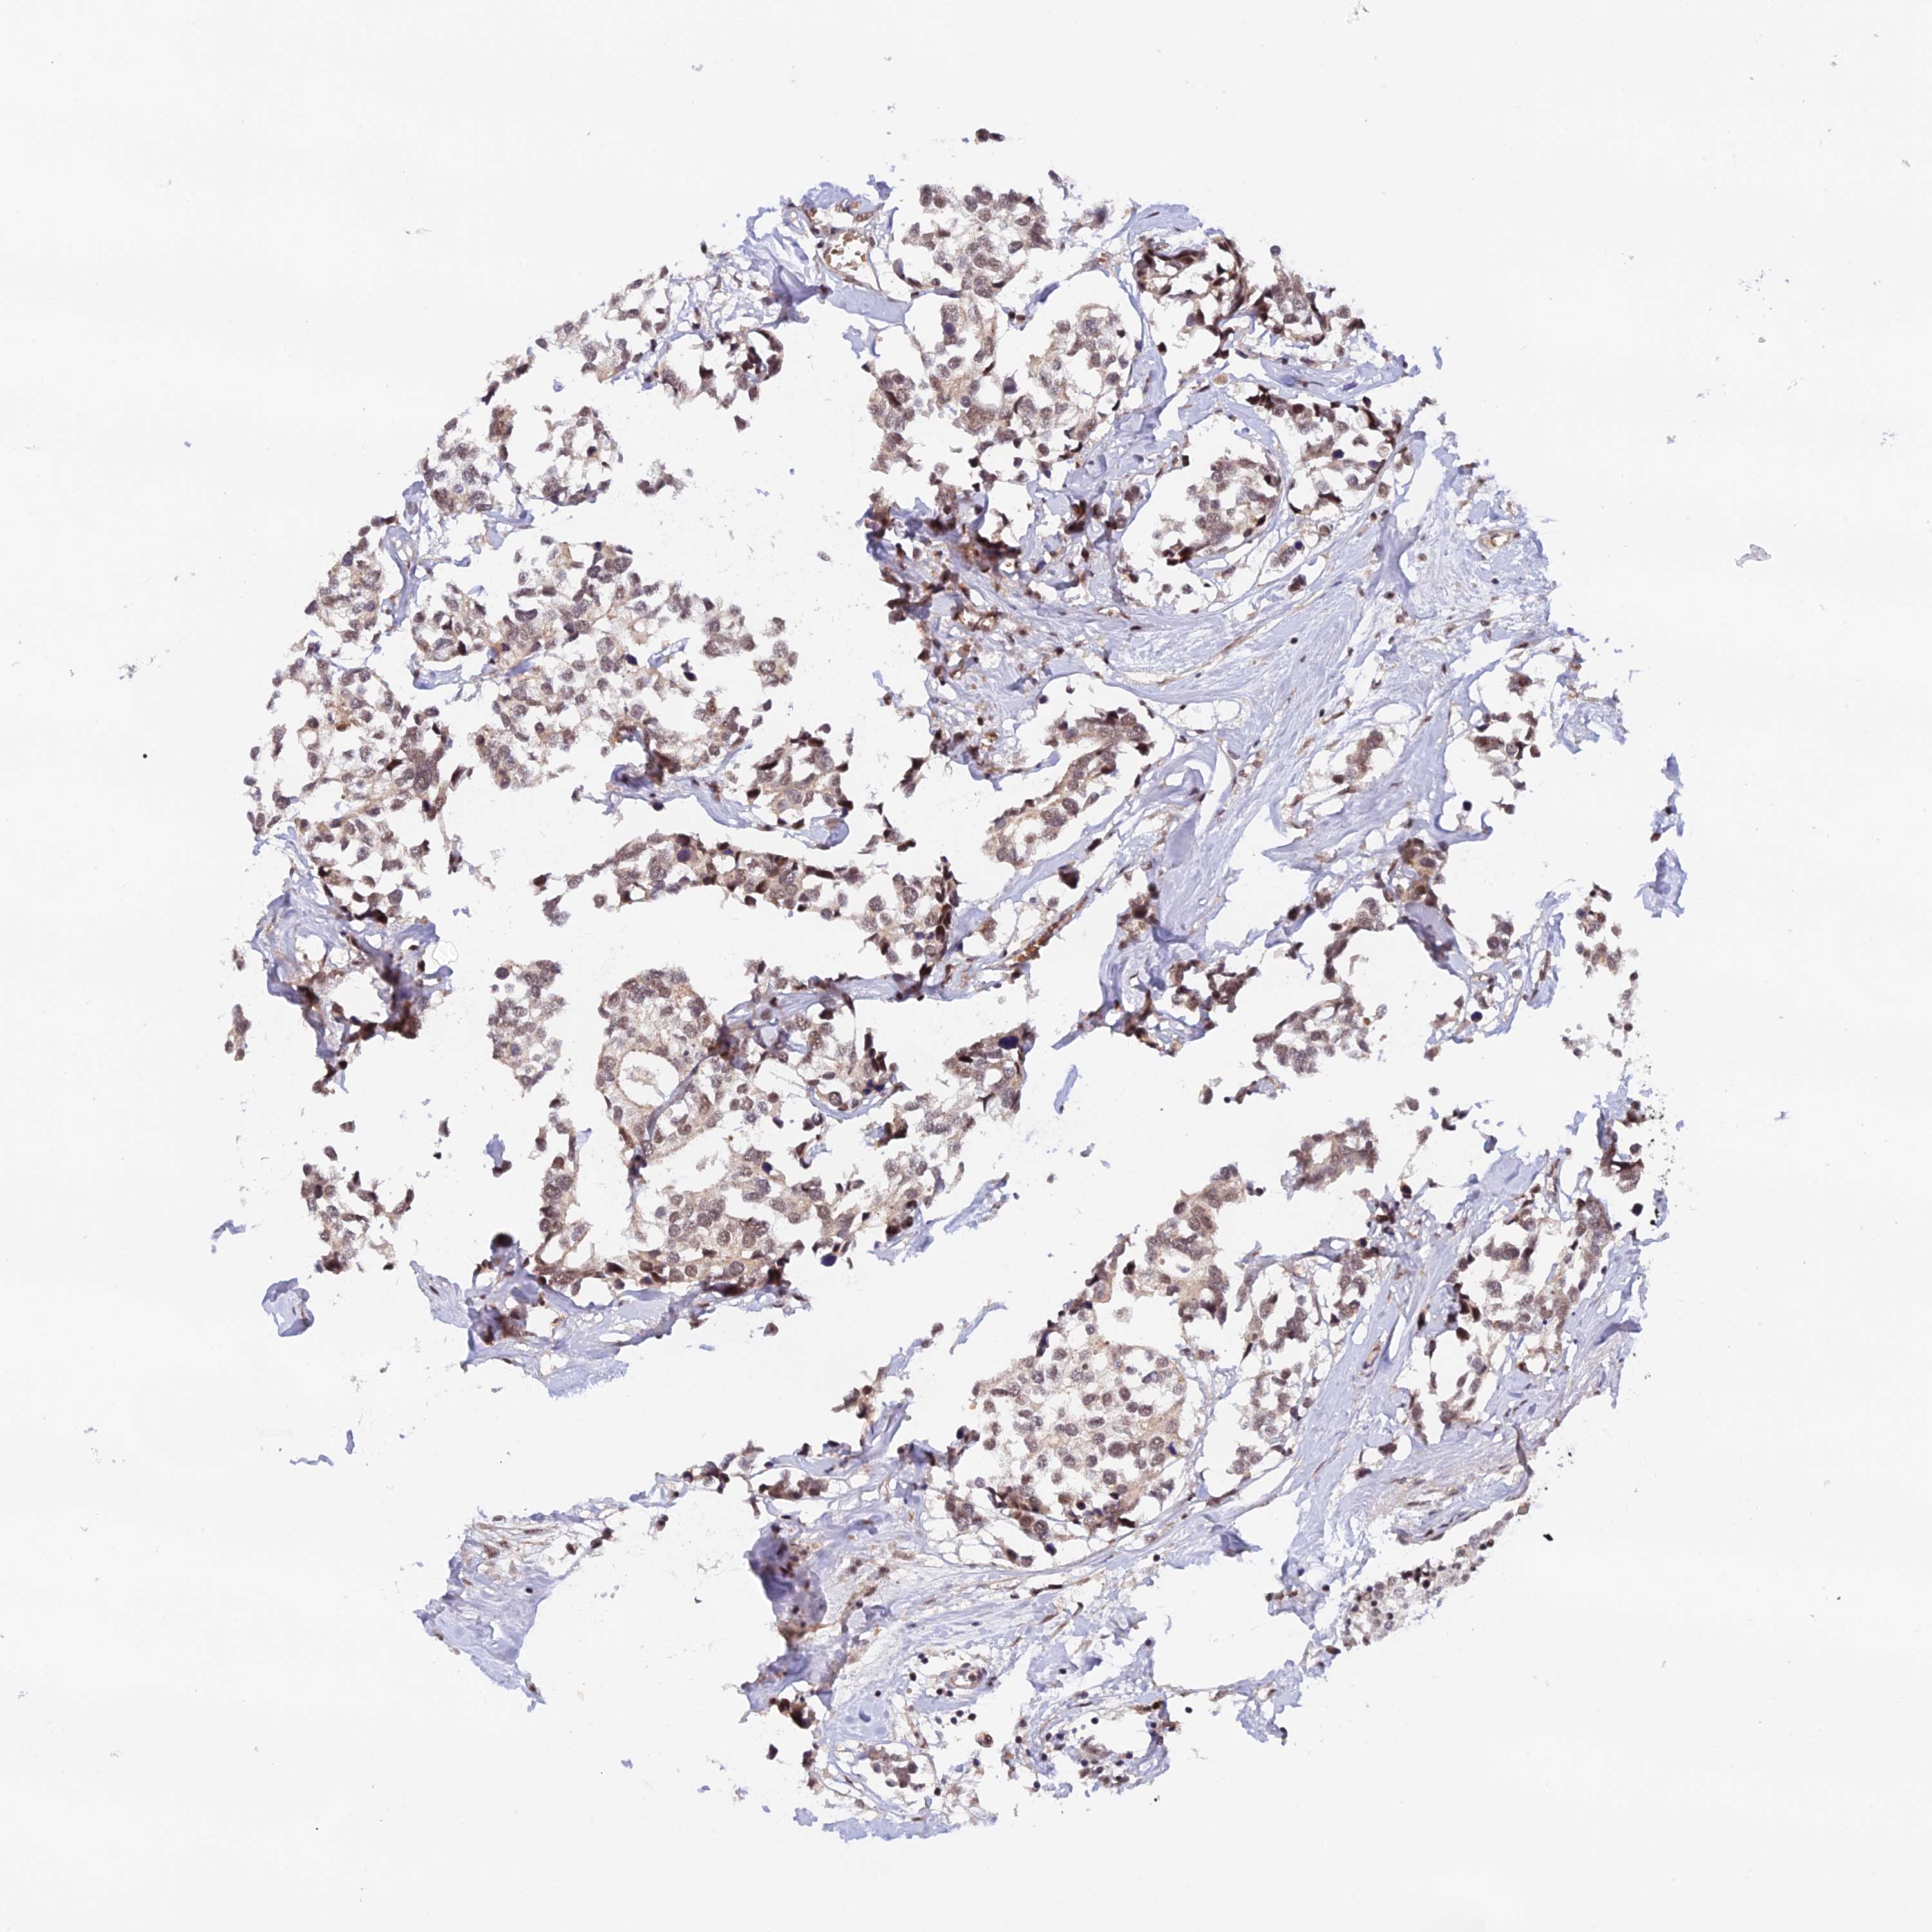

CANCER BREAST CANCER Show tissue menu

BRCA TCGA BRCA VALIDATION PROTEIN EXPRESSION